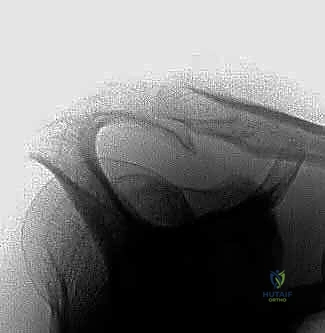

التصوير الطبي:

* الأشعة السينية (X-rays): لتقييم شكل الأخرم (النوع 1، 2، 3) والبحث عن النتوءات العظمية أو التكلسات.

أشكال عظم الأخرم (تصنيف بيجلياني Bigliani)

يلعب شكل عظم الأخرم دوراً حاسماً في احتمالية الإصابة بالانحشار. صنف الطبيب بيجلياني الأخرم إلى ثلاثة أشكال رئيسية بناءً على صور الأشعة السينية:

* النوع الأول (المسطح - Flat): مساحة واسعة تحت الأخرم، خطر ضئيل جداً للانحشار.

* النوع الثاني (المنحني - Curved): انحناء طفيف لأسفل، يقلل المساحة، خطر متوسط للانحشار وتمزق الأوتار.

* النوع الثالث (المعقوف - Hooked): ينحني بشكل حاد لأسفل مثل الخطاف، يضيق المساحة بشدة، ويرتبط بشكل وثيق جداً (أكثر من 70%) بتمزقات الكفة المدورة وانحشار الكتف الشديد.

الهدف الأساسي من جراحة "تجميل الأخرم" (Acromioplasty) هو تحويل الأخرم من النوع الثاني أو الثالث المعقوف، إلى النوع الأول المسطح، لتوفير مساحة آمنة للأوتار.